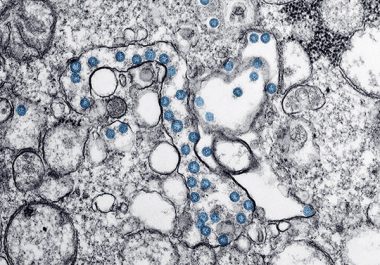

Experts offer information and cancer centers take precautions in light of the novel coronavirus, and the Food and Drug Administration approves an immunotherapy combination for liver cancer.